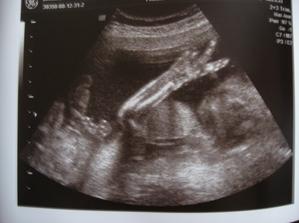

10.12. genetický ultrazvuk ve 20.týdnu, prý mimčo nemá nic navíc ani mu nic nechybí 🙂

31.12. 4D ultrazvuk, máme krásné fotečky a krátké filmiky s prckem, škoda jen, že si schovával hlavičku. Asi se nerad fotí, stejně jako tatínek 🙂. Pohlaví jsme si vydrželi nenechat říct, prý tam je v jednom filmu letmo vidět, ale já jako laik to fakt nepoznám.